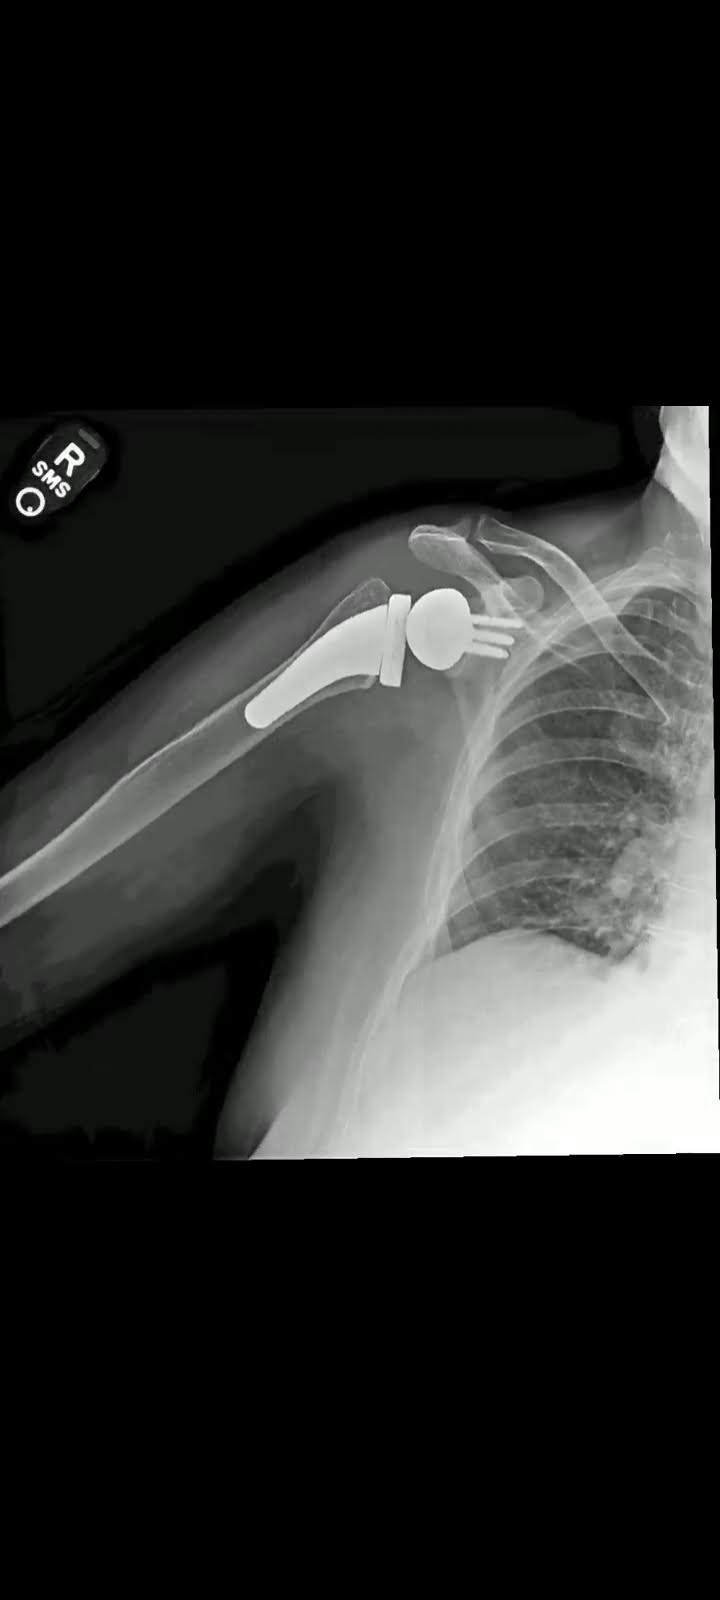

Shoulder replacement, or shoulder arthroplasty, is a surgical procedure where a damaged or arthritic shoulder joint is replaced with a prosthetic implant. This procedure is recommended for individuals suffering from chronic shoulder pain due to arthritis, rotator cuff injuries, or degenerative conditions. Dr. Lokesh Yogi and his team at Jaipur Ortho are leaders in minimally invasive shoulder replacement surgery, offering precise treatment plans for faster recovery and long-term success.

- Total Shoulder Replacement: Replacement of both the ball and socket of the shoulder joint.

- Reverse Shoulder Replacement: Specialized procedure for patients with rotator cuff damage.